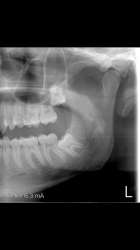

tmp18296-Screen[...].png (788Кб, 1080x1920)

>>567782

Вот вторая.

Дёсна везде придётся резать.

Я этого не особо боюсь, самое главное чтоб корни никуда не затолкали.

И челюсть не выломали, лол.

Вообще задумываюсь, стоит ли их все вырывать...

боли вообще нет во время операции, после конечно ноет но на обезбаливающих терпимо. но у меня нижние вообще горизонтально были, десну резали и долбали прилично чтоб достать, у тебя может даже и резать не прийдется.